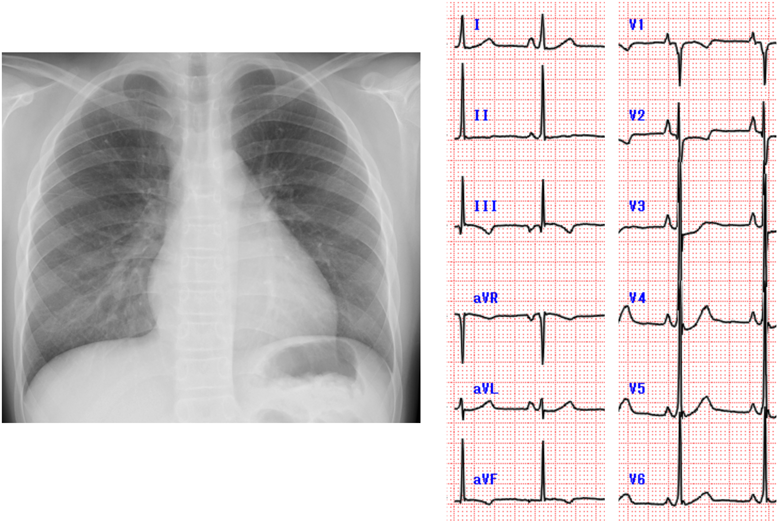

On a chest X-rays, the CTR was 51%, and the pulmonary vascular shadow was normal. Electrocardiogram showed right atrium enlargement (Fig. 2).

The CTR was 51%, and pulmonary congestion was none. Electrocardiogram showed right atrium enlargement.